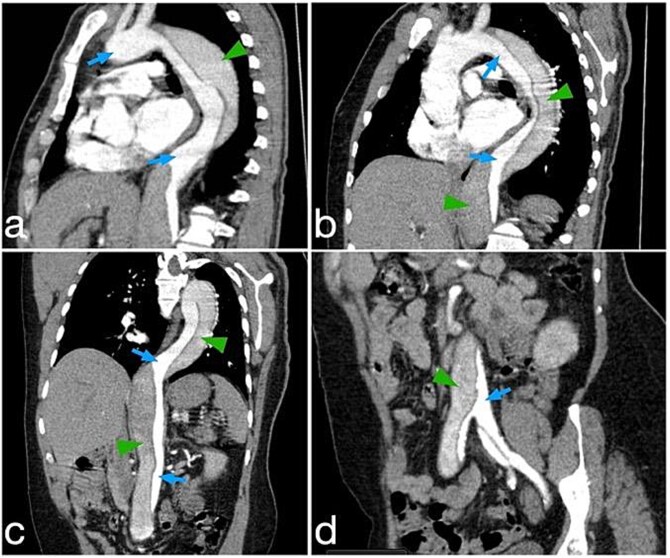

咯血是源自下呼吸道的血液的咳痰,有广泛的鉴别诊断,从良性疾病到危及生命的疾病,包括肺栓塞、严重感染和主动脉夹层。我们报告一位53岁男性,有高血压、慢性阻塞性肺病和吸烟史,以两天咯血史就诊于急诊科。尽管没有胸痛等典型症状,但胸部x线片显示纵隔增宽,并进行了增强CT血管造影。CT扫描证实是斯坦福B型主动脉夹层。在多学科审查后,医疗管理决定降压药和氨甲环酸。患者血流动力学保持稳定,并被转入进一步治疗。本病例提示,即使没有典型症状,主动脉夹层也应列入咯血的鉴别诊断。

Hemoptysis is the expectoration of blood originating from the lower respiratory tract and has a wide differential diagnosis, ranging from benign conditions to life-threatening diseases that include pulmonary embolism, severe infections, and aortic dissection. We present a 53-year-old male with a history of hypertension, COPD, and smoking, presenting to the emergency department with a two-day history of hemoptysis. In spite of the absence of classical symptoms such as chest pain, his chest X-ray showed mediastinal widening, and further imaging was performed with contrast-enhanced CT angiography. The CT scan confirmed a Stanford Type B aortic dissection. After multidisciplinary review, medical management was decided upon with antihypertensive medications and tranexamic acid. The patient remained hemodynamically stable and was transferred for further management. This case indicates the inclusion of aortic dissection in the differential diagnosis of hemoptysis, even without classic symptoms.